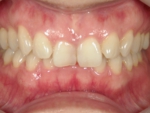

叢生(そうせい)

歯の生えるスペースが足りなかったり歯が大きいために、でこぼこに生えたり、重なって生えている状態です。乱杭歯(らんぐいば)ともいいます。犬歯が飛び出た状態の八重歯(やえば)も叢生の一種です。